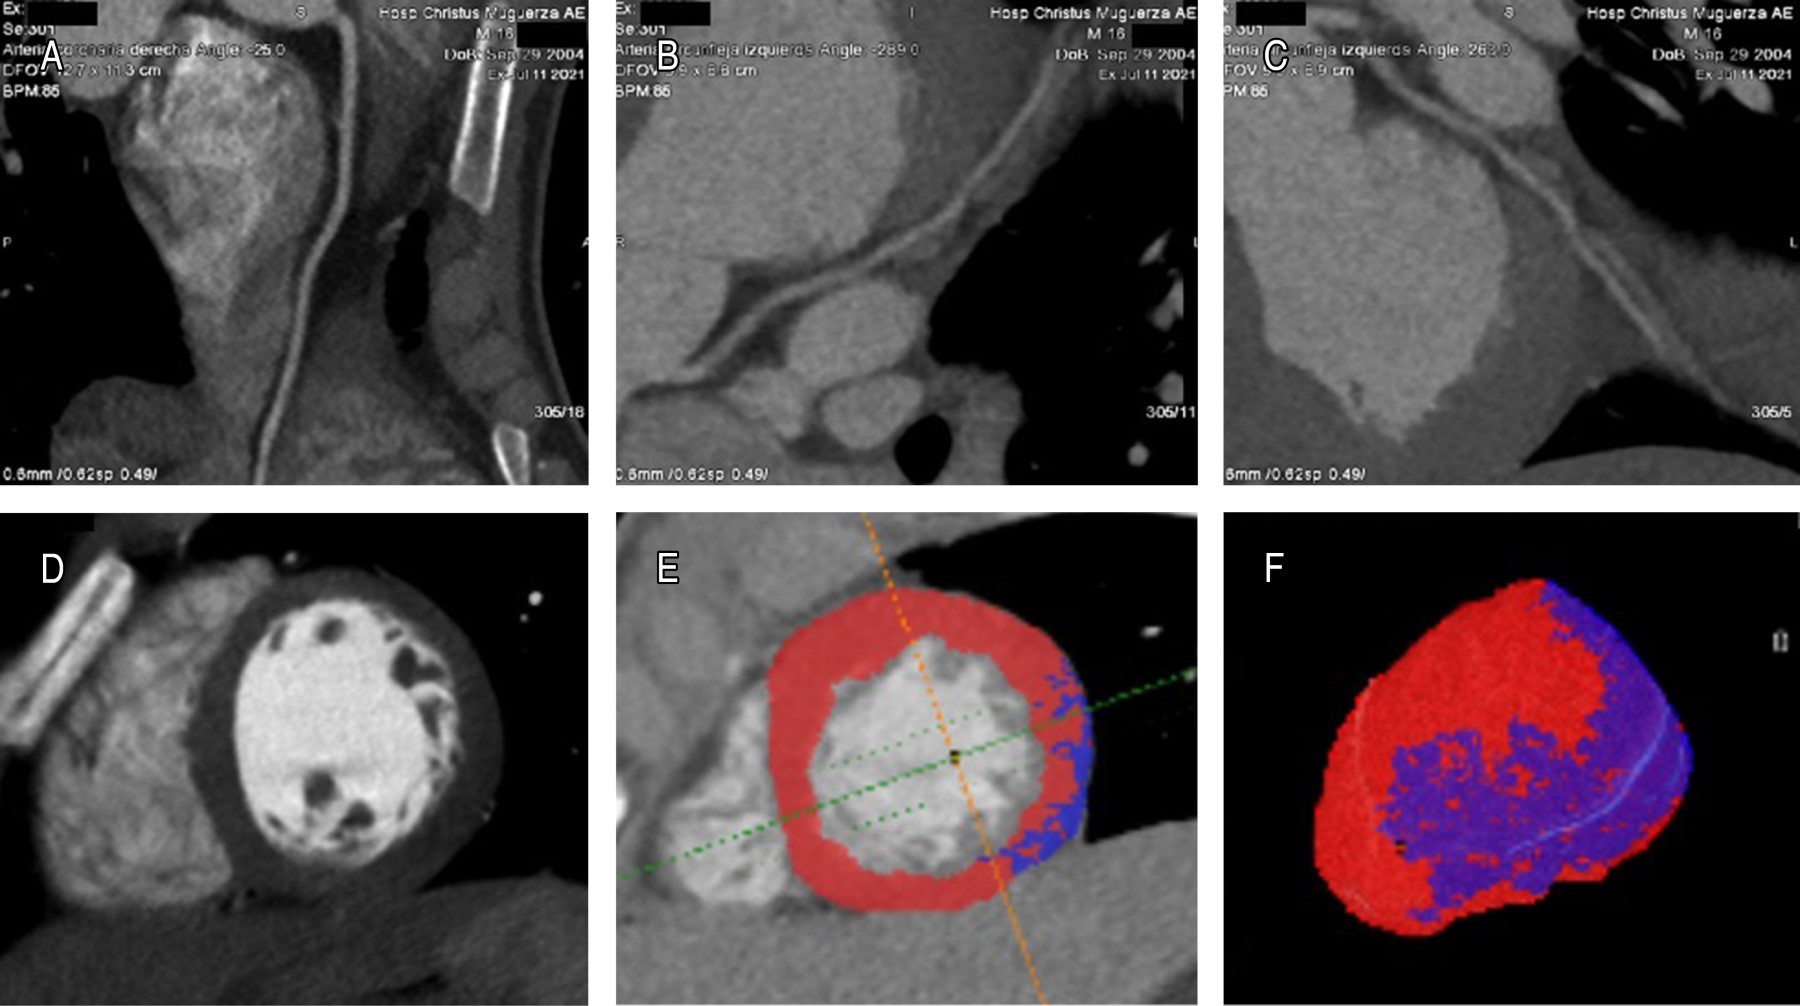

La miocarditis es una condición inflamatoria multifactorial del miocardio. La miocarditis ha sido reconocida recientemente como un evento adverso, en pacientes vacunados contra COVID-19 con Pfizer-BioNTech y Moderna (vacunas de ARNm), principalmente en adolescentes y adultos jóvenes. La resonancia magnética cardiaca (RMC) permite caracterizar el tejido miocárdico y la función cardiaca y se ha convertido en el estándar de oro no-invasivo en pacientes con sospecha de miocarditis aguda. Los autores presentan a un paciente masculino de 16 años con dolor torácico punzante tras la segunda dosis de inmunización contra el SARS-CoV-2 con la vacuna BNT162B2 (Pfizer-BioNTech). El electrocardiograma (ECG) mostró elevación del segmento ST y aumento de los biomarcadores de lesión miocárdica. La angiotomografía (AngioTC) mostró signos sutiles de hipoperfusión miocárdica y disfunción ventricular izquierda. Se realizó RMC con gadolinio, identificando hipocinesia global del ventrículo izquierdo (VI), hiperemia por edema miocárdico y realce tardío de gadolinio (RTG) como evidencia de lesión miocárdica y marcadores de lesión inflamatoria intramiocárdica no-isquémica. Habiendo excluido otras etiologías, se propone que esta presentación de miocarditis aguda sea una reacción adversa asociada a la vacuna BNT162b2 contra COVID-19. Los riesgos a largo plazo de la vacuna contra la COVID-19 en niños, adolescentes y adultos jóvenes aún se desconocen, por lo que será necesario seguir investigando.

Figura 1